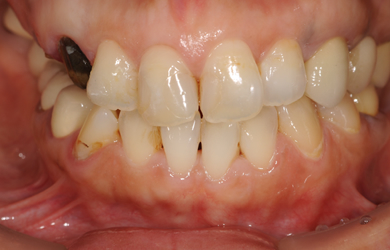

治療後

• 治療後

治療内容 インプラント5本(抜歯即日スピードインプラント+サイナスリフト+GBR+クラウンレングスニング)、ハイブリッドセラミック8本

総治療費 2,426,400円

治療期間 9.5ヶ月